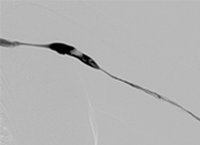

Case CLI with right foot ulcer thrombectomy: Posterior and anterior tibial

Case CLI with Right Foot Ulcer Thrombectomy pre-procedure arteriogram.

Arteriogram of posterior and anterior tibial post-CDT

PT and AT remained occluded following overnight CDT infusion of lytic

Case CLI with Right Foot Ulcer Thrombectomy post-AngioJet Solent Dista.

Post-AngioJet™ Solent™ Dista thrombectomy with PowerPulse™ delivery

AngioJet Solent Dista Catheter used in Power Pulse mode in both AT and PT. 30 min dwell in  AT and 45 min dwell in PT. Followed by Solent Dista Catheter used in thrombectomy mode

Case CLI with Right Foot Ulcer Thrombectomy post-procedure arteriogram.

Post-procedure arteriogram

Image following ballooning of small focal lesion in PT